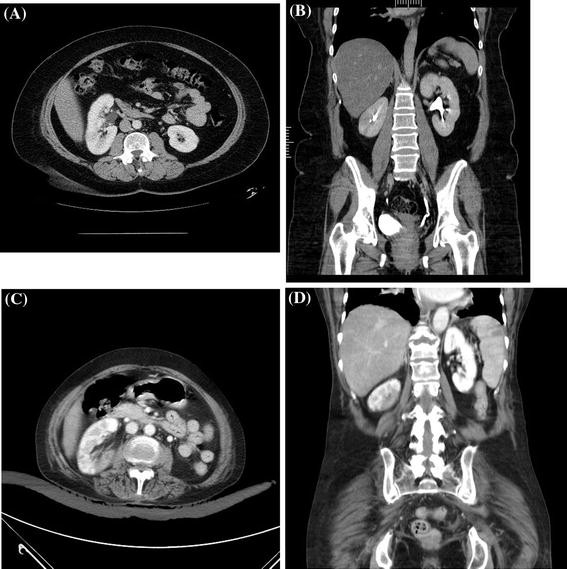

The white arrows outline a large cecal neoplasm. Filed under abdomen, anatomy, ct, pelvis. And so, just to orient everybody before we go through the images and the coronal plane, up. After completing this laboratory exercise you should feel comfortable identifying abdominal and pelvic organs and blood vessels on axial and coronal ct there are few important muscles in the abdomen and pelvis.